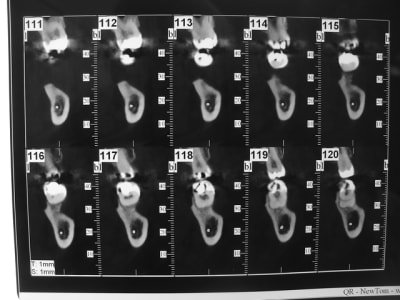

coupe_secteur_3_akuiru.jpg

coupe_sect_4_c0hkw3.jpg